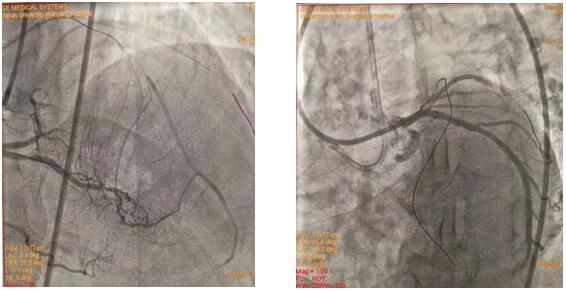

(插圖說明:圖1為雙側(cè)造影圖、圖2為導絲正向通過圖、圖3為求那邊、圖3為球囊通過圖、圖4為導絲逆向通過圖)

在吳棟梁院長的協(xié)調(diào)安排下,從12月24日清晨7:30到12月25日清晨7:50安全完成62例介入手術(shù)。其中,心血管內(nèi)科二病區(qū)介入團隊在左梅主任的帶領(lǐng)下,清晨七點半開始,C3830電極對于左束支區(qū)域起搏、永久起搏器的成功置入,逆向技術(shù)開通LAD近段無殘端閉塞病變的順利完成,創(chuàng)造著一個個生命的奇跡,為心血管病患者帶來一個不平凡的平安夜。